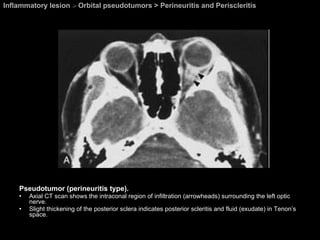

Inflammatory lesion  >  Orbital pseudotumors > Perineuritis and Periscleritis Pseudotumor (perineuritis type).  Axial CT scan shows the intraconal region of infiltration (arrowheads) surrounding the left optic nerve.  Slight thickening of the posterior sclera indicates posterior scleritis and fluid (exudate) in Tenon’s space.

Perineuritis and Periscleritis Orbital pseudotumors  Idiopathic perineuritis = inflammation of the sheath of the optic nerve Can simulate optic neuritis by presentation (orbital pain, pain with extraocular motility, decreased visual acuity, and disc edema).

Perineuritis and Periscleritis Orbital pseudotumors  CT and MR imaging: A ragged, edematous enlargement of the optic nerve sheath complex.